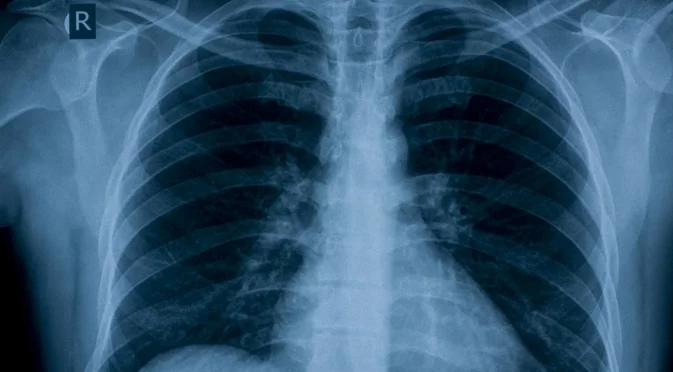

Ракът на белите дробове е толкова опасно заболяване, че превенцията и информираността за симптомите му са от изключително значение.

Най-лошото е, че това заболяване се открива късно, в напреднал стадий, поради леки симптоми. Ето защо е много важно да знаете основните симптоми, които могат да показват рак на белите дробове и да отидете на лекар възможно най-скоро